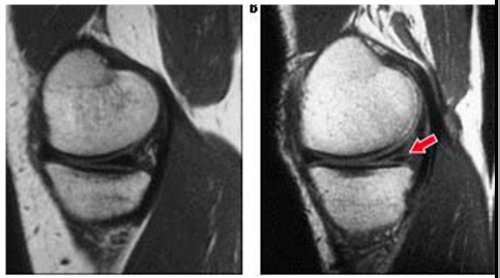

Магнитно-резонансная томография (МРТ) — это неинвазивный метод диагностики, который визуализирует костные структуры на экране компьютера. Этот томограф способен обнаруживать даже незначительные нарушения в целостности хрящей. Патологические изменения менисков отображаются на экране и анализируются врачом-специалистом. Метод основан на послойном сканировании тканей, а создание качественного изображения осуществляется благодаря магнитному полю. В процессе происходит эффект ядерного резонанса, в котором участвуют протоны атомов мениска. Энергия, выделяемая в ходе этого процесса, фиксируется специальным датчиком, а изображение формируется с помощью цифровой обработки.

Результаты магнитно-резонансной томографии позволяют различать начальную стадию повреждений и более серьезные состояния. Линейные сигналы повышенной интенсивности, не выходящие за пределы хряща, указывают на повреждение мениска второй степени. При этом анатомическая структура костной ткани остается неизменной, хрящ не отрывается и сохраняет свою форму.

Наиболее тяжелая стадия патологического процесса требует повышенного внимания как со стороны врача, так и пациента. Важную роль играют своевременное обращение за медицинской помощью и профессионализм ортопеда. Третья степень заболевания характеризуется полным разрывом мениска коленного сустава. При этом сигналы высокой интенсивности имеют горизонтальную направленность и достигают поверхности хряща. Анатомическая структура нарушается, что четко видно на МРТ. В медицине выделяют подстепень 3а, которая включает не только отрыв, но и смещение хряща.